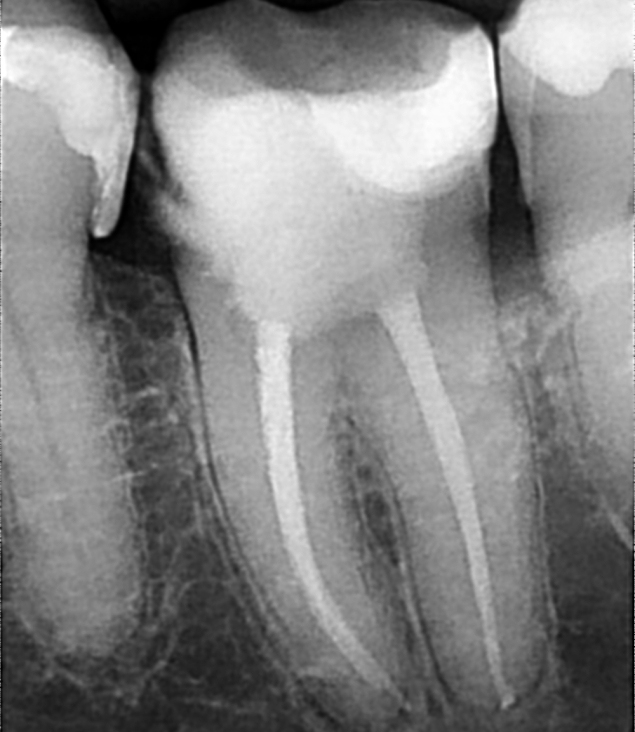

Terapija se sastoji od zahvata kojim se takav inficirani zub otvara, čisti

od karijesa te posebnim instrumentima ulazi u kanale koji se čiste od

infekcije. Korijenski kanali pune se biokompatibilnim materijalom koji brtvi

i onemogućuje reinfekciju endodontskog prostora.